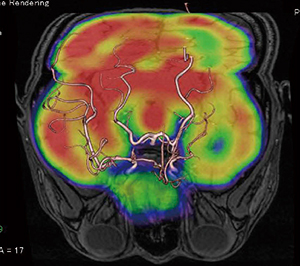

図7 もやもや病

脳血流シンチグラフィ(123I-IMP)と

MRAのフュージョン画像